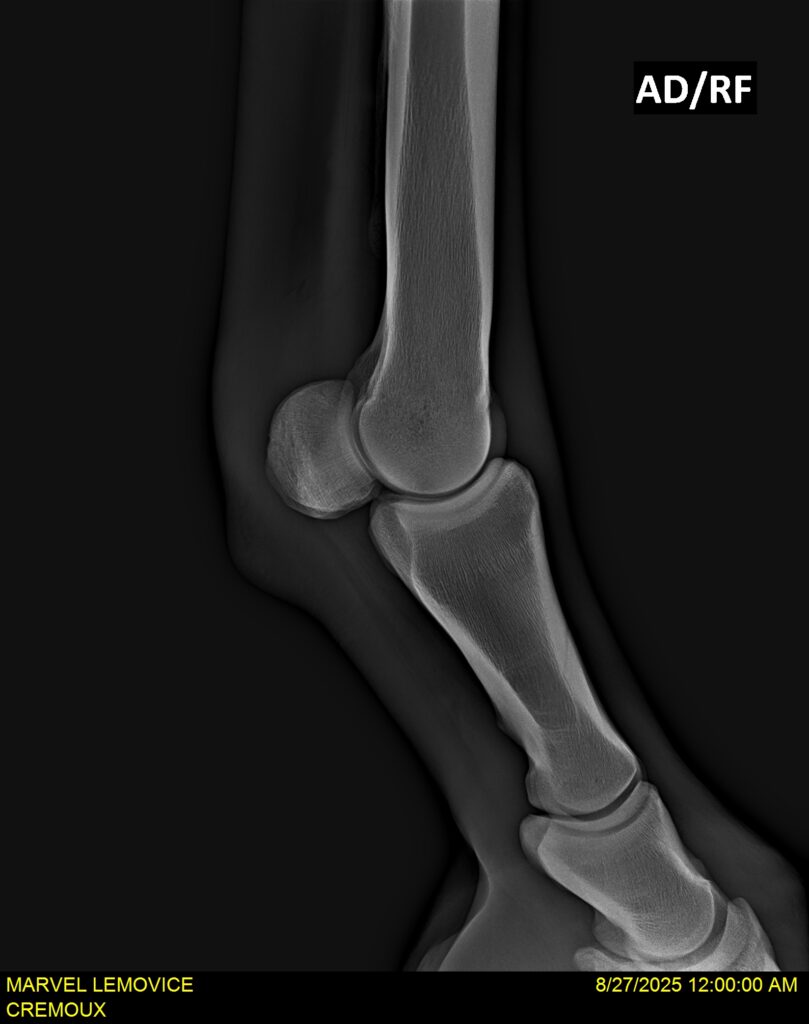

MARVEL LEMOVICE, hongre, Selle Français prend 4 ans en 2026. POPSTAR LOZONAIS x ROSIRE sur une excellente souche maternelle de l’élevage PLATIERE. Débourré aux trois allures et mise en route à l’obstacle. Super modèle avec du cadre et de la force, cheval respectueux avec des moyens. Très agréable au quotidien. Transport OK, maréchalerie OK, santé RAS, Bilan 20 clichés radios + clinique OK.

RADIOS ET CLINIQUE